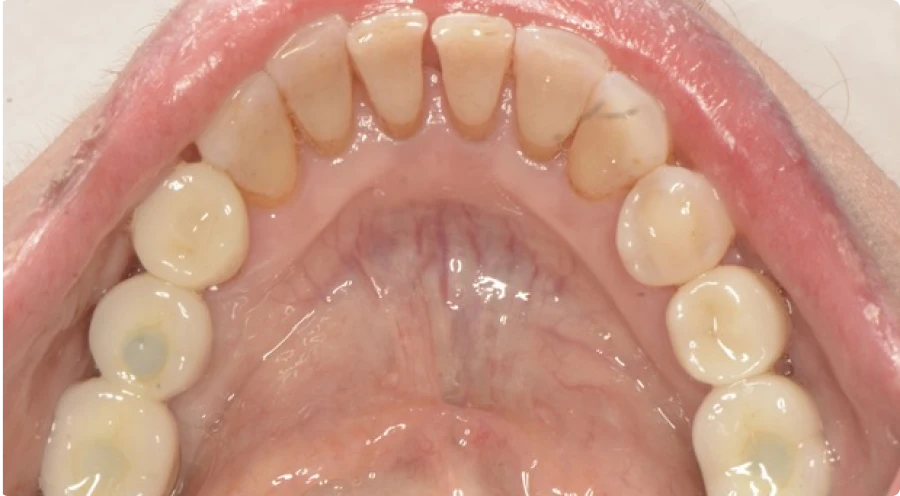

Pour illustrer l’impact de nos traitements, voici quelques exemples concrets de réhabilitations globales réalisées au cabinet Horizon Sourire. Ces cas cliniques montrent différentes situations où des traitements multidisciplinaires ont permis à nos patients de retrouver une santé dentaire optimale. Chaque photo présente l’évolution avant et après les soins, mettant en évidence les résultats fonctionnels et esthétiques obtenus. Ces exemples démontrent notre approche globale, personnalisée et coordonnée, visant à restaurer la mastication, améliorer l’apparence du sourire, et renforcer la confiance de nos patients. Découvrez ces transformations qui témoignent de notre engagement à offrir des soins dentaires de qualité.